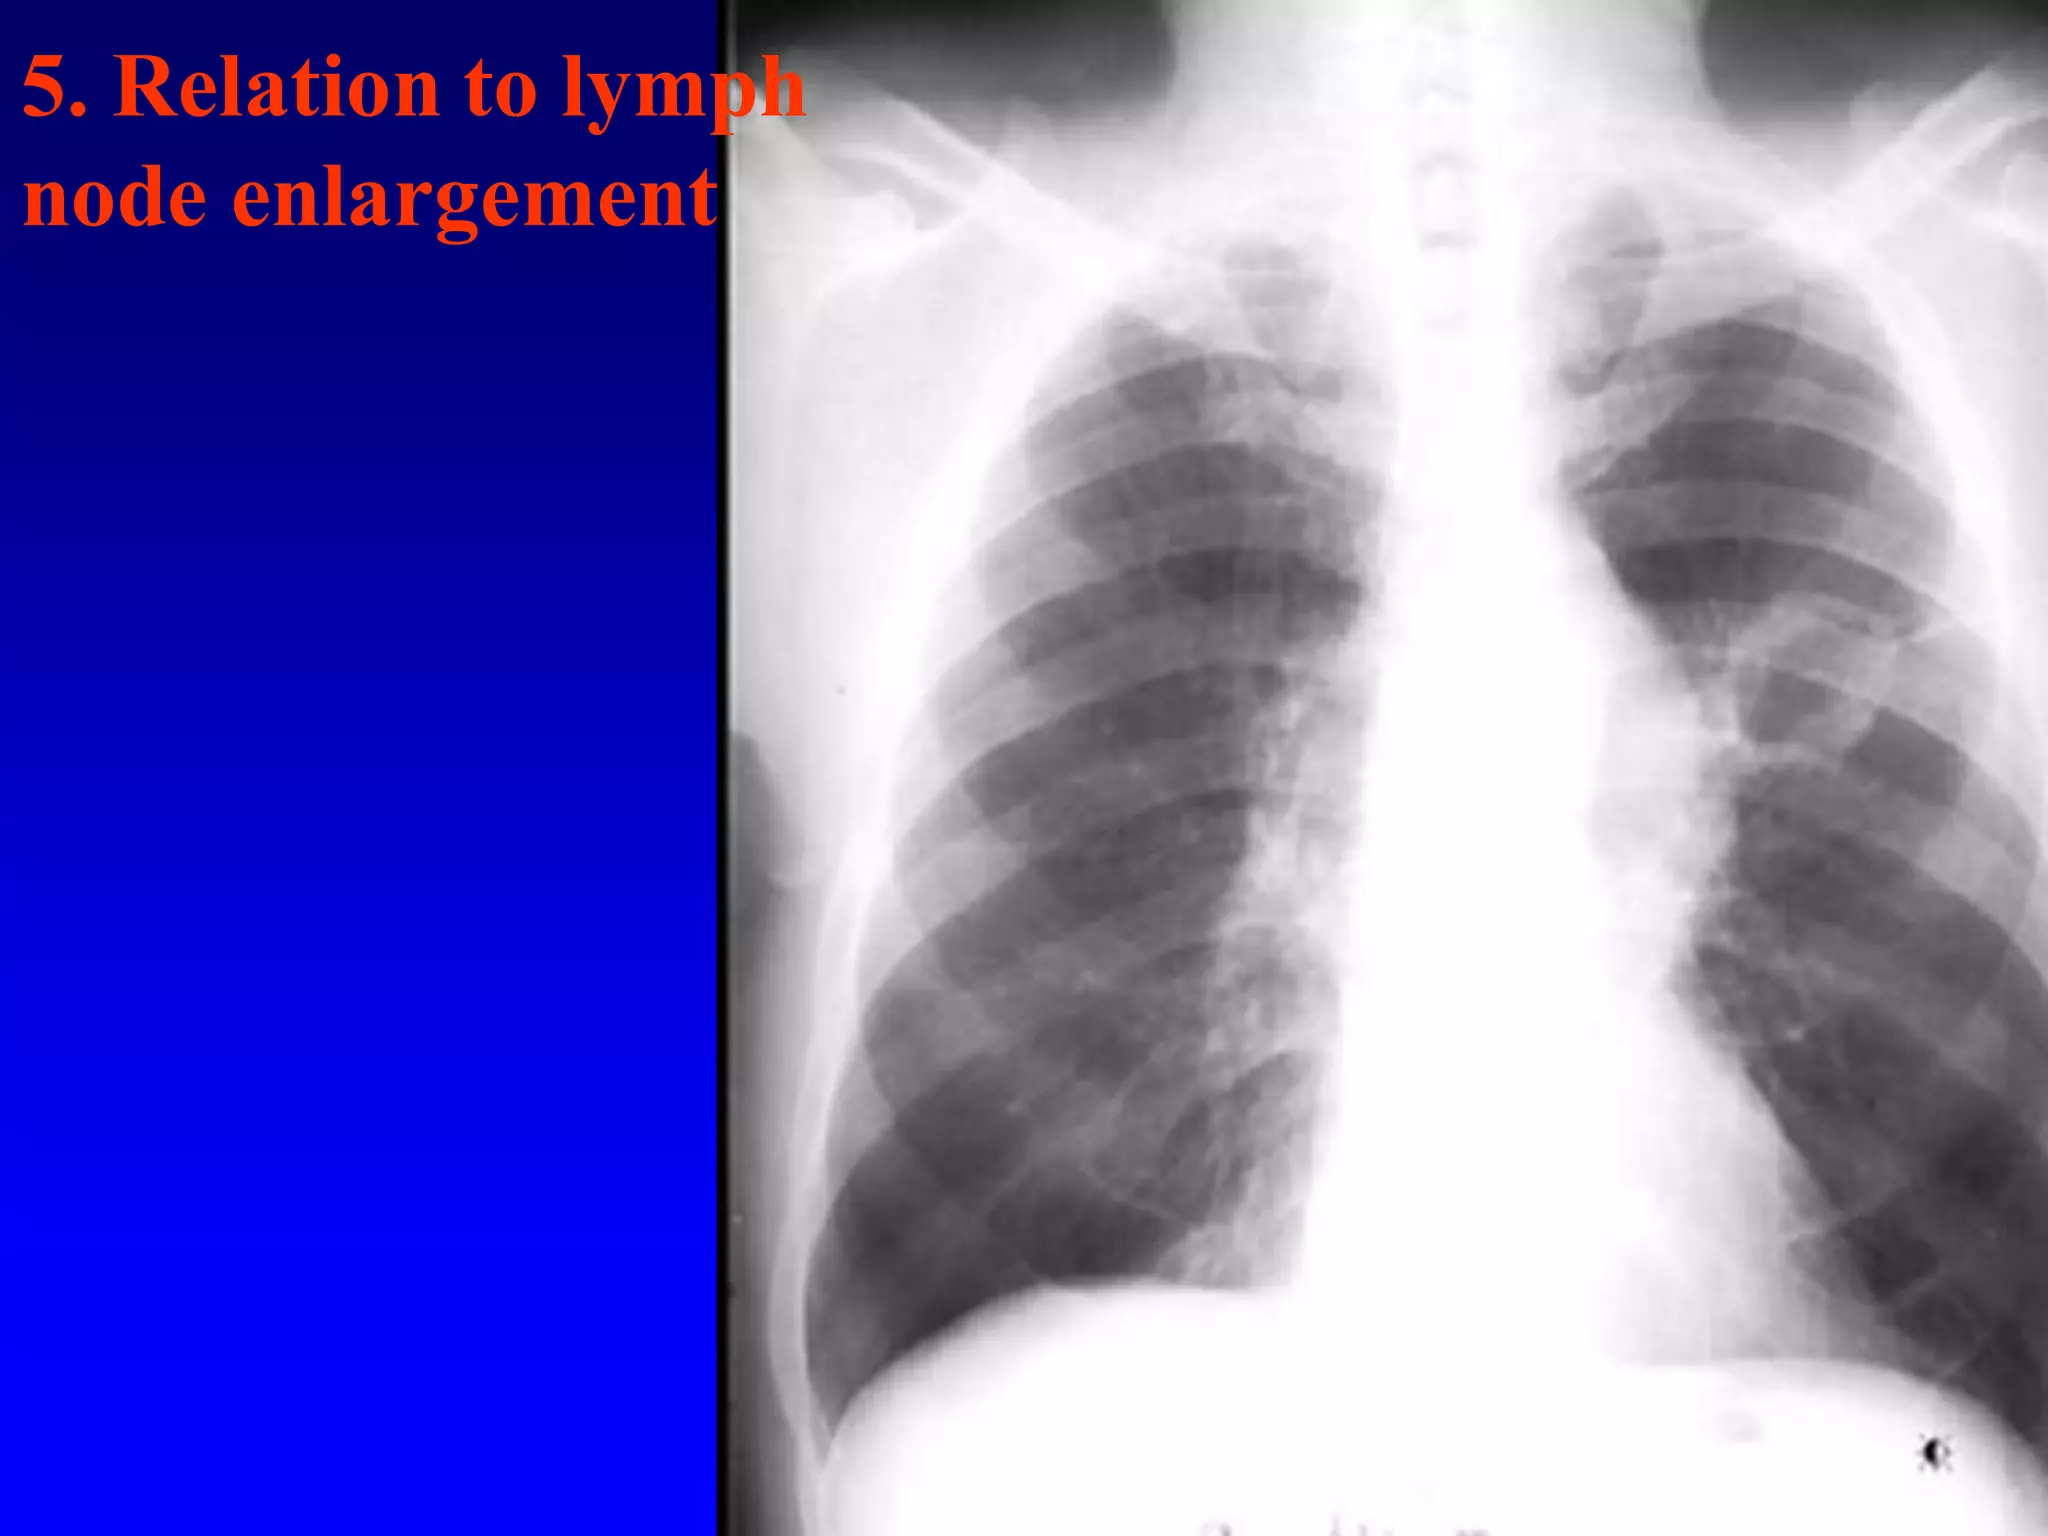

5. Relation to lymph

node enlargement

5. Relation tolymph node enlargement